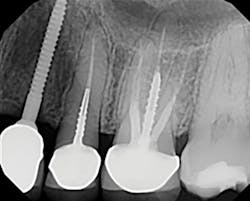

A 32-year-old male presented with a congenitally missing lateral, No. 10. The buccal-lingual dimensions were sufficient for standard implant placement, but the mesial-distal dimensions were 4.56 mm (figures 1a and 1b). The patient had a failing Maryland bridge, both functionally and esthetically (figure 2). He was always told that implants were not an option for him unless he underwent significant orthodontic treatment, and even then, nothing was guaranteed.

By selecting a 2.4 mm Anew implant (Dentatus), we were able to preserve sufficient bone between implant and tooth (1.5 mm), allowing for gingiva, a natural emergence profile, and maintaining the papilla in this highly esthetic area. Gingival recontouring was performed with a diode laser (Epic, Biolase). We had the lab fabricate a surgical guide and an immediate screw-retained provisional restoration for flapless implant placement (figures 3 and 4).